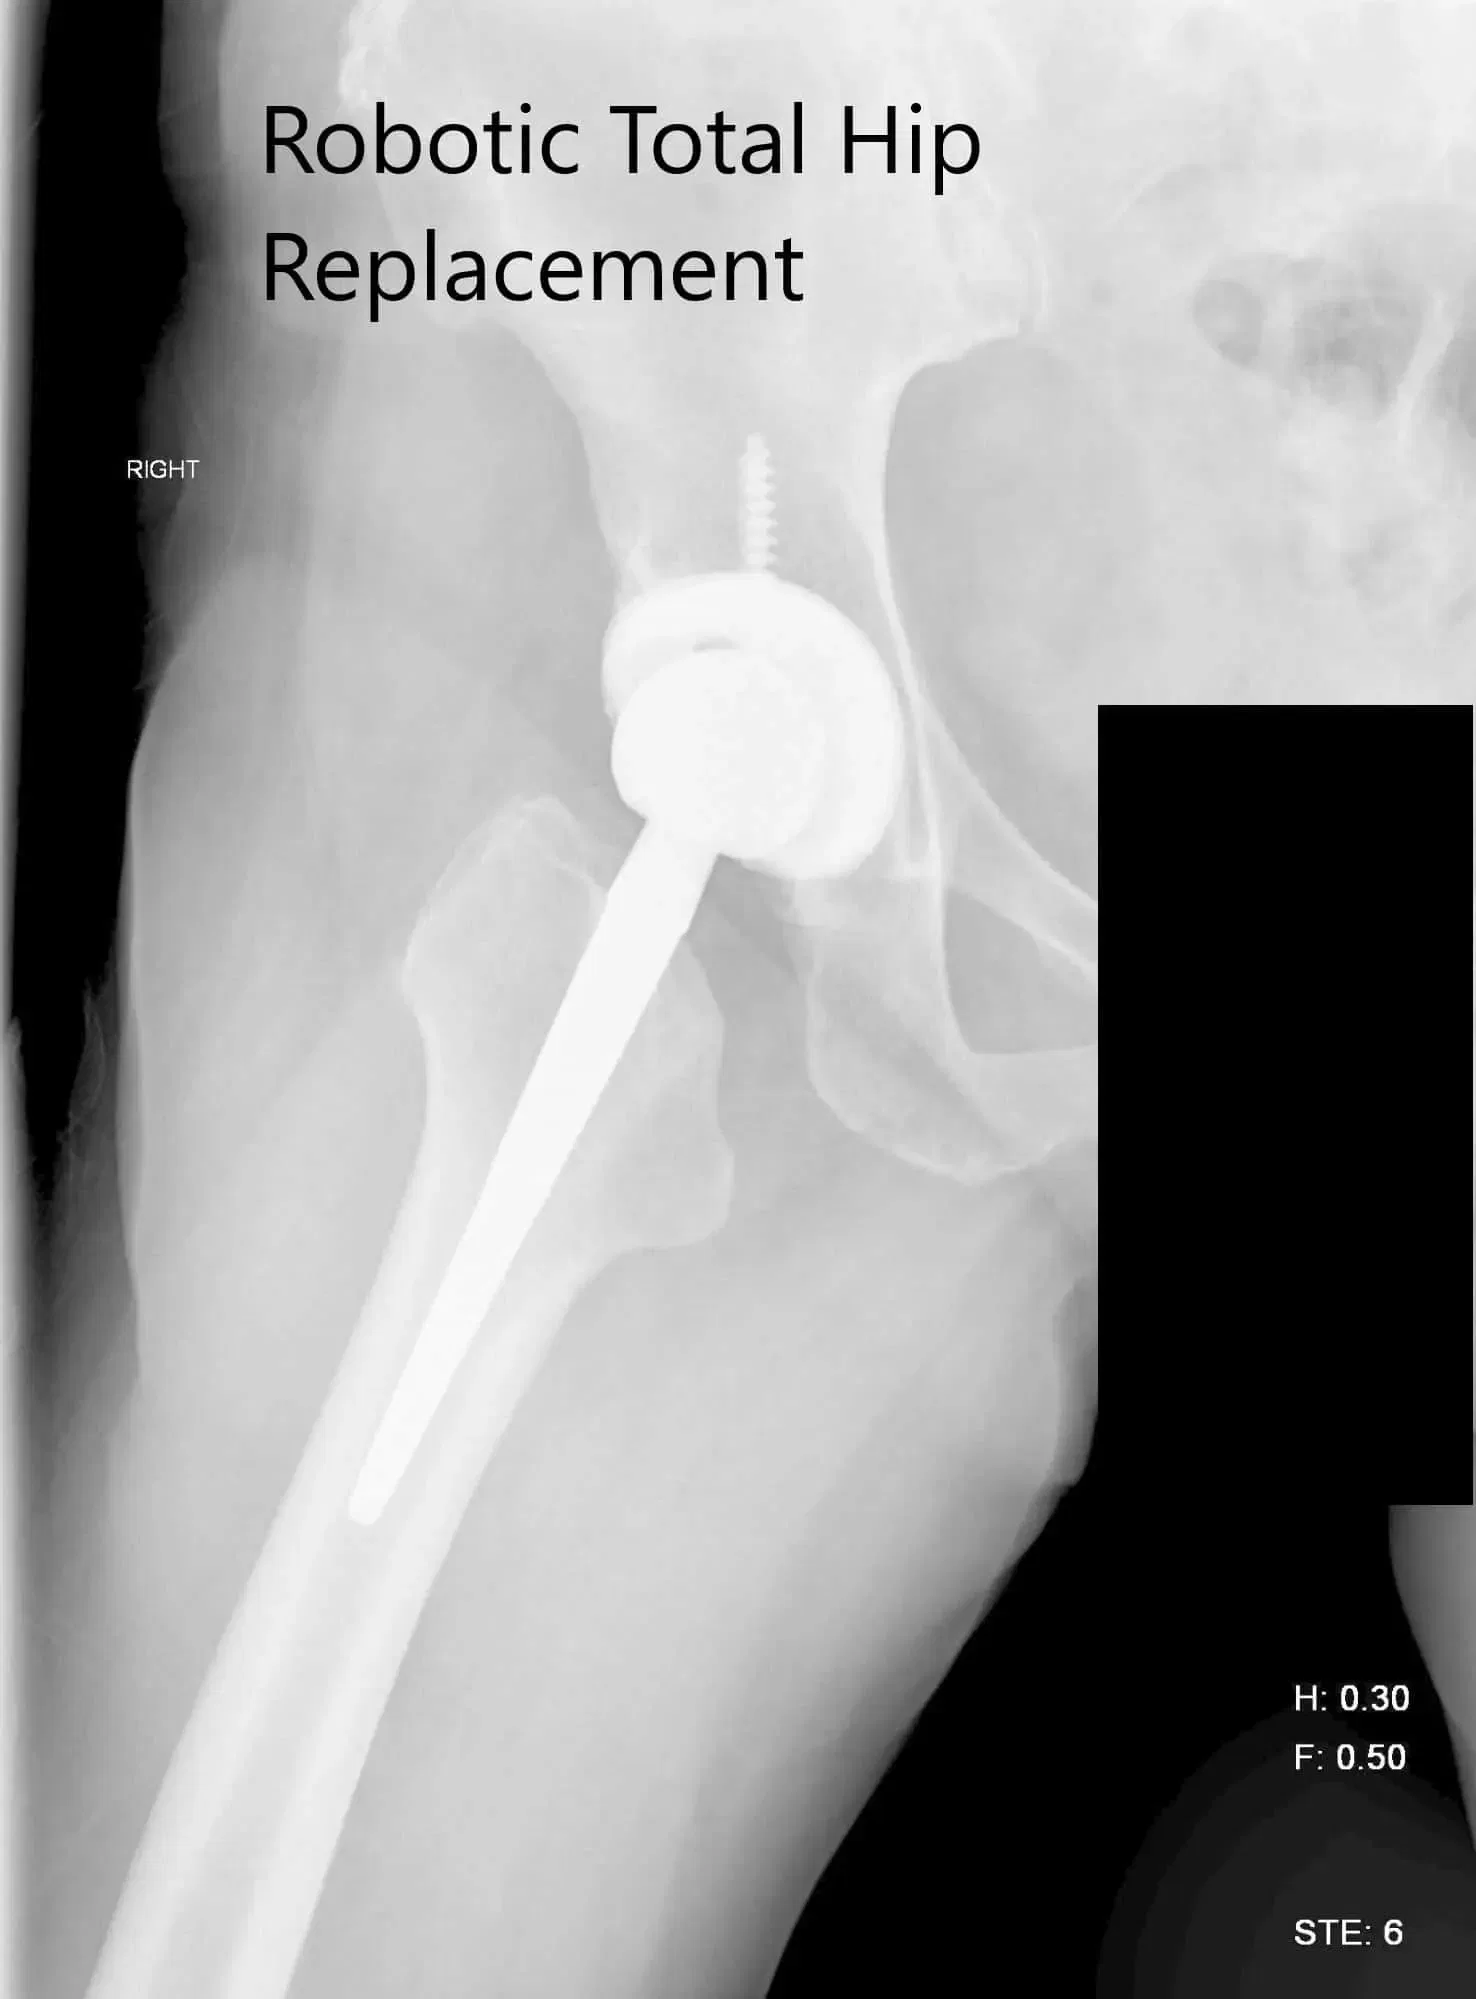

Radiografía preoperatoria que muestra la vista de la parágrafe auricular y lateral de la cadera derecha.

Radiografía postoperatoria de la cadera derecha que muestra visión AP y lateral.